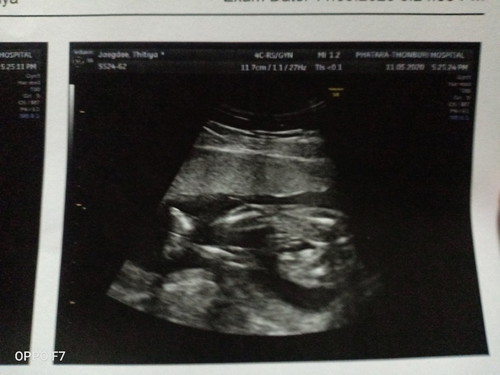

ดูออกกันมั้ยค่ะ ว่าน้องเป็นเพศอะไร

แม่พึ่งไปซาวด์มาเมื่อวานเองค่ะ 20wk

น่าจะสาวน้อยนะคะ ไม่เห็นป๋องแป๋งกับไข่ค่ะ

คิดว่าผู้หญิงนะคะ เรียบกริบเลย😂😂😂

บ้านนี้ทายว่าหญิง

น้องเป็นผู้หญิง 💕💕